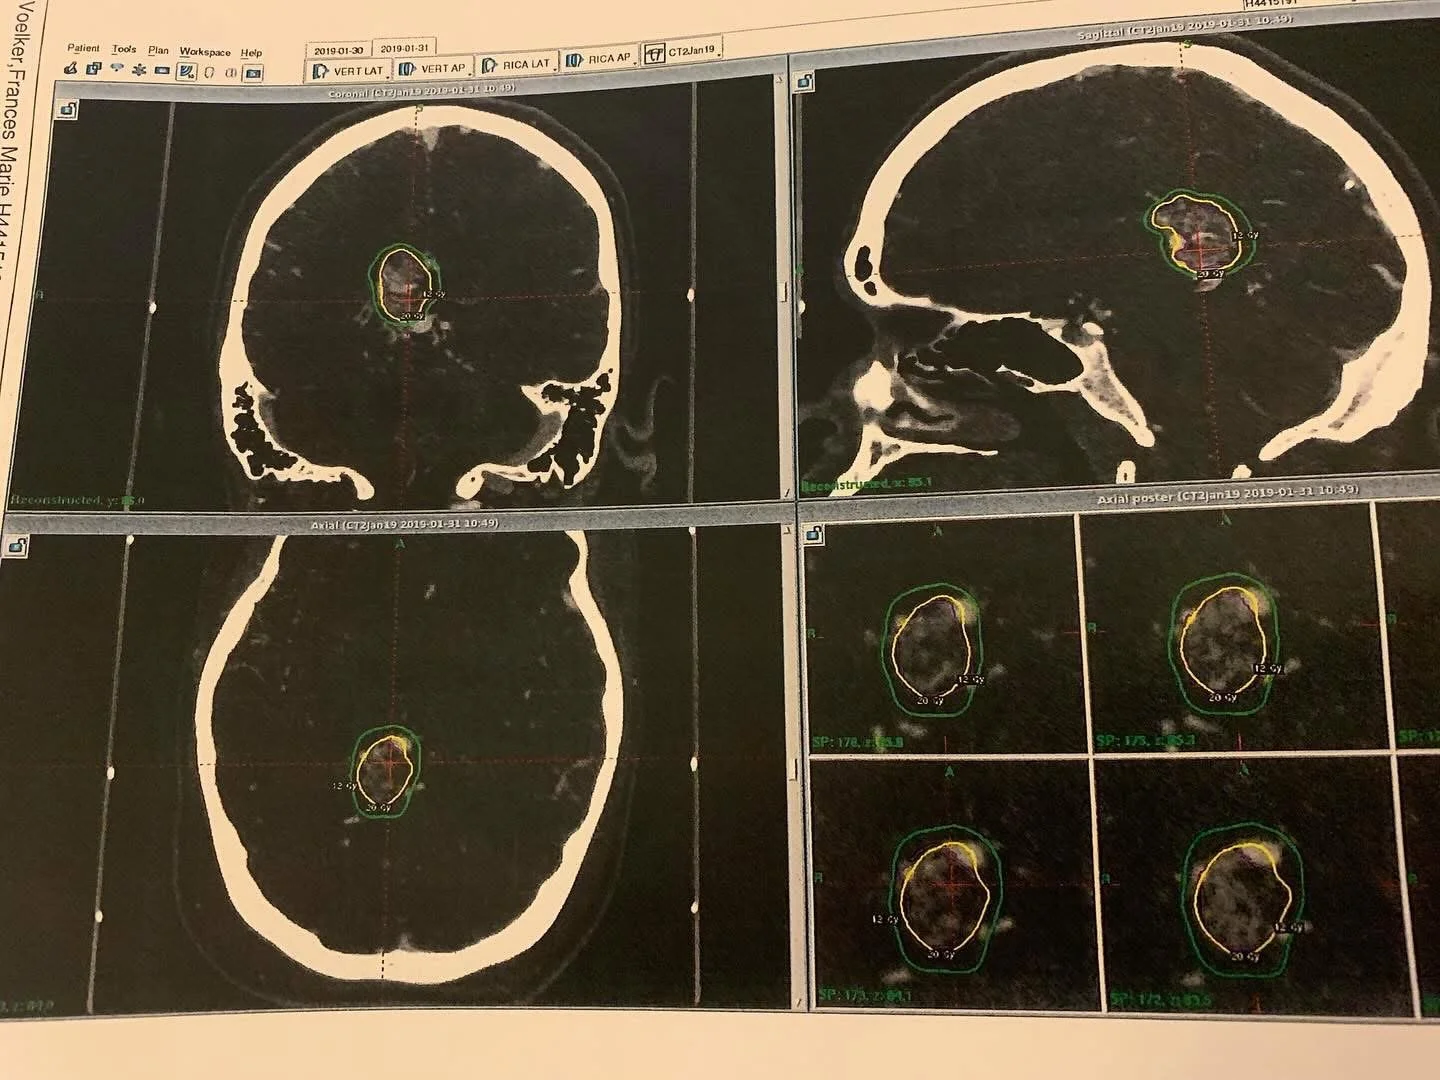

MRI imaging of a cerebral arteriovenous malformation (AVM), showing a complex nidus of abnormal, tangled blood vessels in the brain. This high-grade (Spetzler-Martin Grade 5) AVM carries a significant risk of rupture, necessitating precise intervention and ongoing monitoring.

A Life-Threatening Diagnosis: Grade 5 AVM

Further evaluation revealed the full picture:

Spetzler-Martin Grade 5 AVM (the highest severity level)

Located in the posterior corpus callosum, deep within the brain

Considered inoperable at the time due to size and location

The AVM carried an estimated 3% risk of rupture per year, compounded annually since birth — which translated to a 78% lifetime risk of rupture by the time I was diagnosed.

Gamma Knife Radiation: Hope and Risk

In January 2019, I underwent Gamma Knife radiosurgery — a focused radiation treatment designed to gradually shrink the AVM and reduce the risk of rupture.